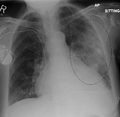

- Normal AP CXR

AP CXR showing left lower lobe pneumonia associated with a small left sided pleural effusion

AP CXR showing right lower lobe pneumonia

AP CXR showing pneumonia of the lingula of the left lung

Right upper lobe pneumonia as marked by the circle.- Left upper lobe pneumonia with a small pleural effusion.

- Right lower lobe pneumonia as seen on a lateral CXR